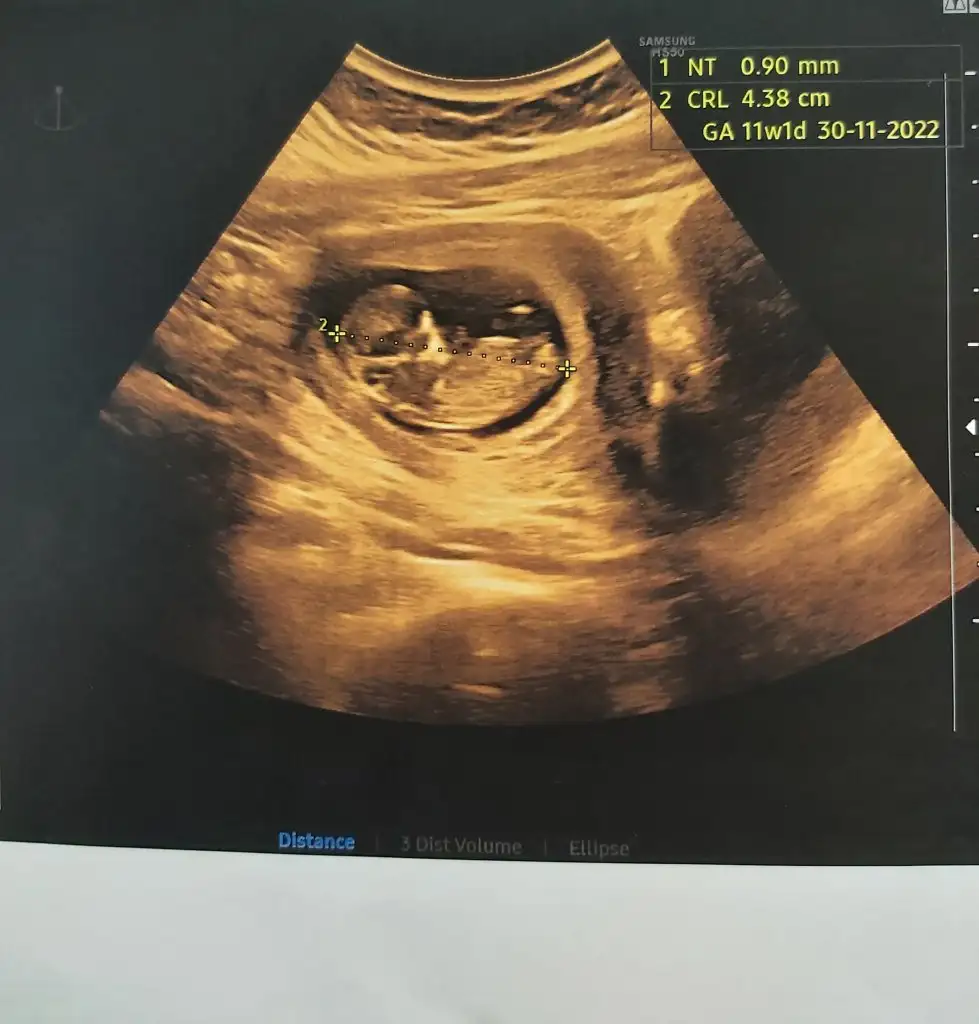

erkek gibiCanım selam 11+1 karından

erkek gibi